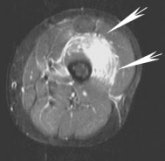

| Same patient, sagittal MRI, FSEIR. Arrows point to the vastus intermedius. Just as on the ultrasound, focal fluid collections surrounded by diffuse muscle edema are visible. |

The protocol for the MR scan included images in the axial plane, T2-weighting, fast spin echo (FSE), and fat saturation. As with the ultrasound, focal fluid collections were surrounded by diffuse muscle edema.